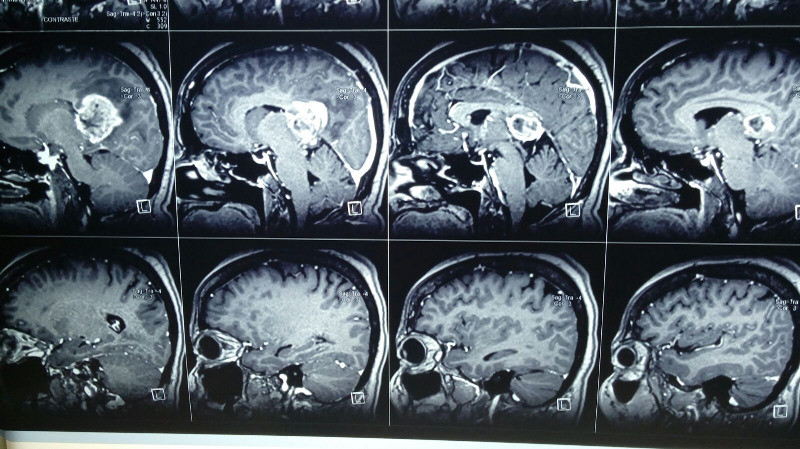

Paciente femenina de 55 años con tumoracion pineal con extencion superior lateral derecha